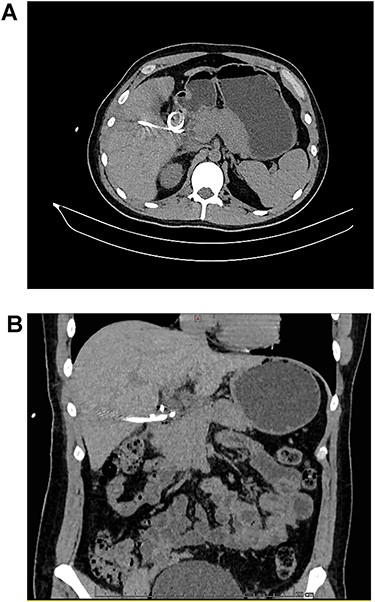

A fistulogram using the catheter was completed, which confirmed our diagnosis. As the patient remained in good condition and asymptomatic, the duodenal perforation was considered contained and conservative management was decided (Fig. 3). Total parental nutrition and NPO (nil per os) were started and the output of the drain dramatically diminished. On the 10th after the diagnosis, the catheter was removed without complications, as the daily output of the drainage did not exceed 50 cc. Sips of clear liquids were initiated immediately, followed by a full diet with no difficulties. He remained completely asymptomatic and was discharged on his 15th day. On follow-up consultations 3 months after the drainage procedure, patient is doing well.

CT reconstruction, the contrast is spreading to the duodenum and small bowel without leaks.